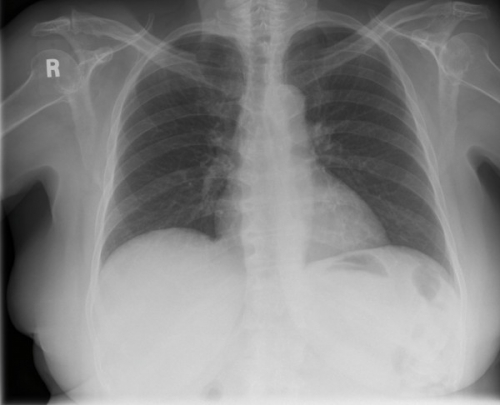

Tool to train medical student's eyes as to what a normal chest x-ray looks like, with over 500 consecutive normal images.